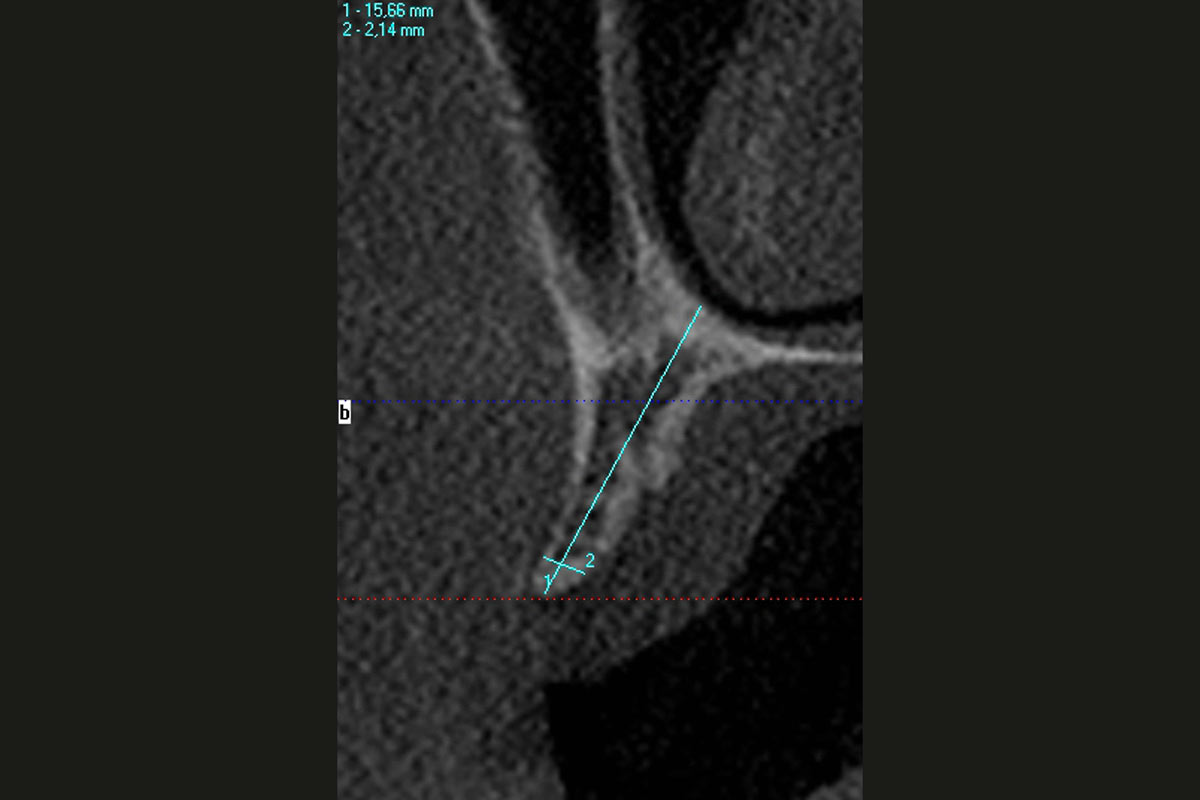

Ridge augmentation in the maxilla with maxgraft® bonebuilder in the aesthetic zone - Dr. M. Kristensen

Bone defect in area 11-21 due to two lost implants (periimplantitis) after 15 years of function